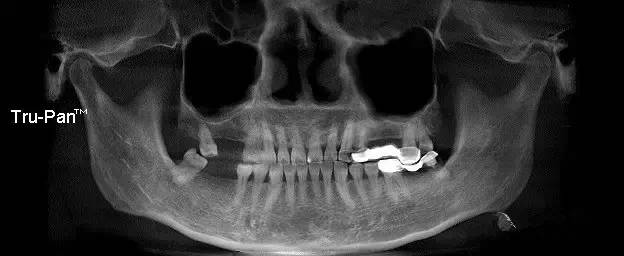

第一圖、臨床上最常見的上頜竇類型之一(高度稍顯不足、上頜竇內(nèi)干凈,提示做上頜竇內(nèi)提升即可)